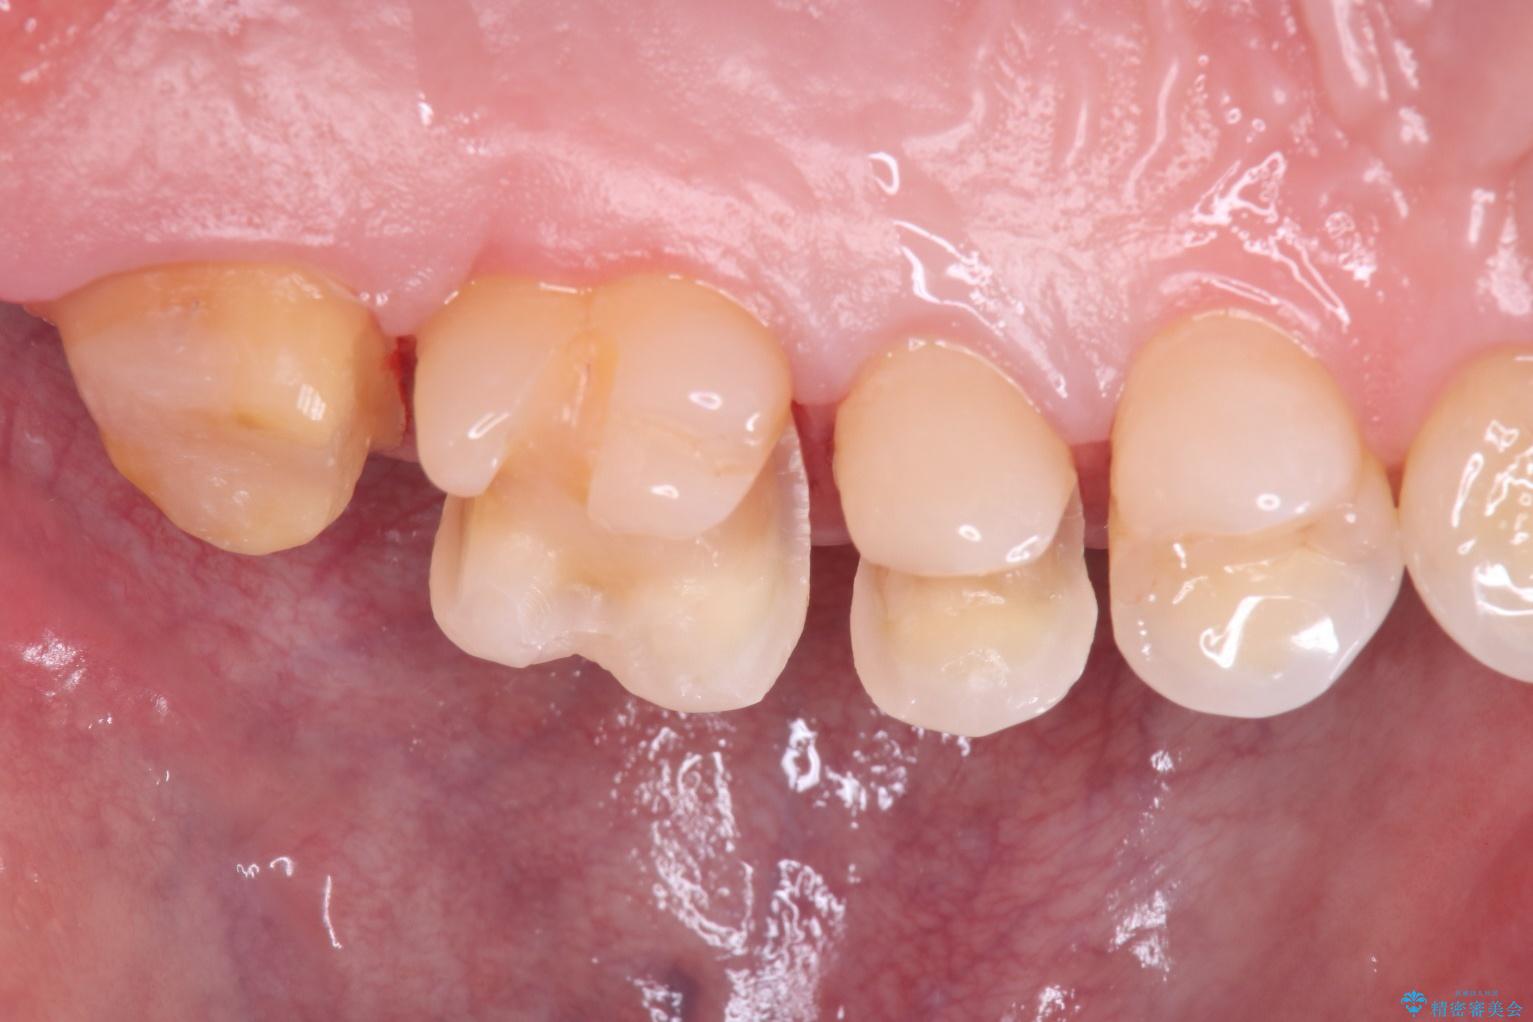

一番奥の歯は銀歯に覆われている範囲が多いため、強度などを踏まえ被せ物にしました。

その他2本は詰め物です。

銀歯が綺麗な白い歯になりました。

適合がとてもよいので、フロスの引っかかりも解消されました。